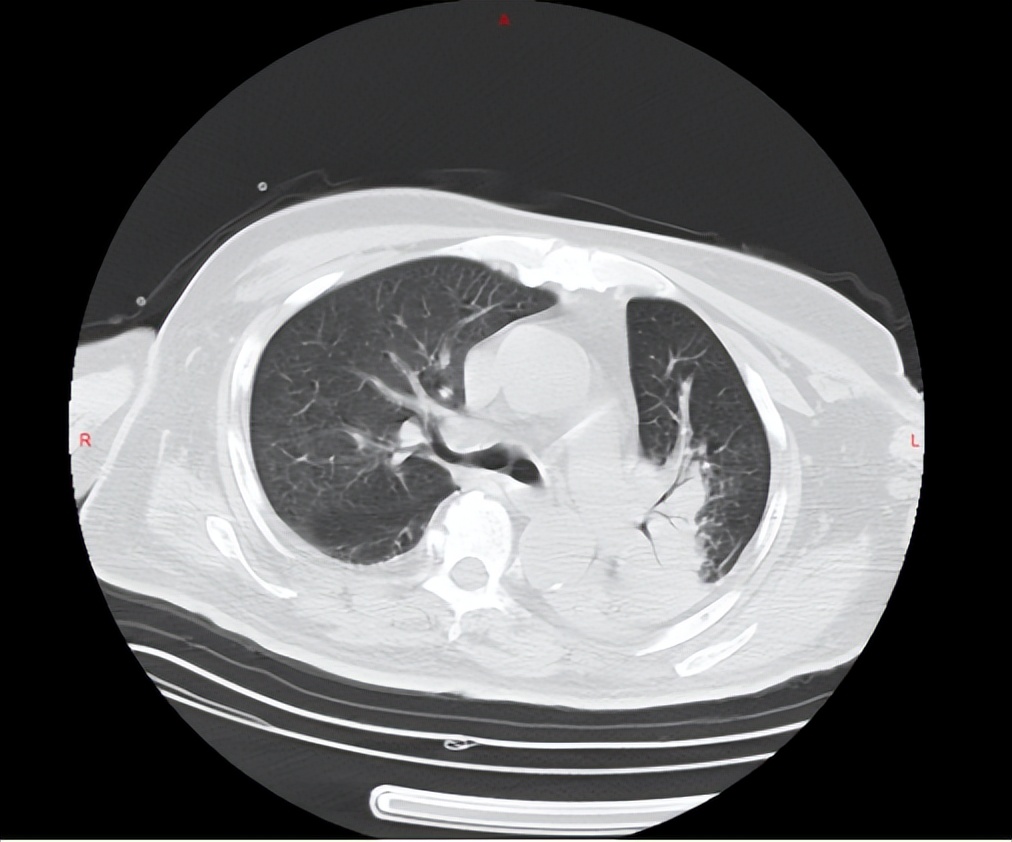

病人为老年男性,近1个月频繁便血,曾多次尝试肠镜检查,但都因肠道准备不佳未能成功,最终病人家属只好求助于鞍钢总医院胃肠外科。病人既往脑血栓病史3年,遗留右侧肢体无法活动,语言不清。因长期卧床、吞咽功能及咳痰能力减弱,病人已出现较为严重的肺炎,吸氧状态下血氧饱和度尚不能完全达标并且病人还患有糖尿病、前列腺增生等多种疾病。

入院后当务之急就是要积极治疗肺炎,解除病人感染、消耗及缺氧的状态;另外通过较为温和长效的缓泻方式清理病人的肠道以完成肠镜的检查;还要给予病人充足的营养来弥补病人长期以来的消耗。最终病人肺炎明显好转,缺氧及营养不良状态得到改善,并完成了肠镜及病理检查,结果回报为结肠肝曲腺癌。